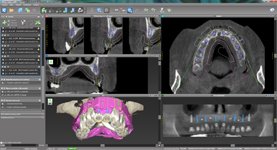

coDiagnostiX – Dental Wings

Jedná se o externí plánovací program, spojený se zubní laboratoří a frézovacím centrem, který využívá dat získaných z 3D rentgenu čelisti, otisku zubů a dásně (scanu zubů a dásně) a finálního návrhu protetické náhrady.

Tento program umožňuje tříprostorovou počítačovou simulaci při plánování pozic implantátů. Součástí programu je i databáze, ve které mohou být uloženy všechny typy implantátů od všech výrobců, včetně jejich délek, průměrů i tvarů.

Lékař si vytvoří všechny typy zobrazení potřebných pro naplánování – tedy 2D snímky (panoramatický), příčné řezy i 3D model.

Vidí zde i důležité anatomické útvary – čelistní dutinu, průběh nervu atd. Po proměření množství kosti – šířky i výšky vybere z databáze vhodný typ implantátu a umístí ho do požadované lokality. Ihned vidí jeho pozici ve všech 3 rovinách a na

všech snímcích i 3D modelu. Může upravovat podle potřeby jeho pozici, sklon atd.

Všechny vybrané a správně umístěné simulované implantáty se ukládají do „počítačové karty“ pacienta s jejich pozicí, délkou, průměrem, typem i sklonem. V programu také lékař navrhuje chirurgické šablony pro řízenou nebo navigovanou implantaci.

Lékař i pacient tedy ještě před vlastní operací vidí, jak by mělo ošetření probíhat a vypadat.